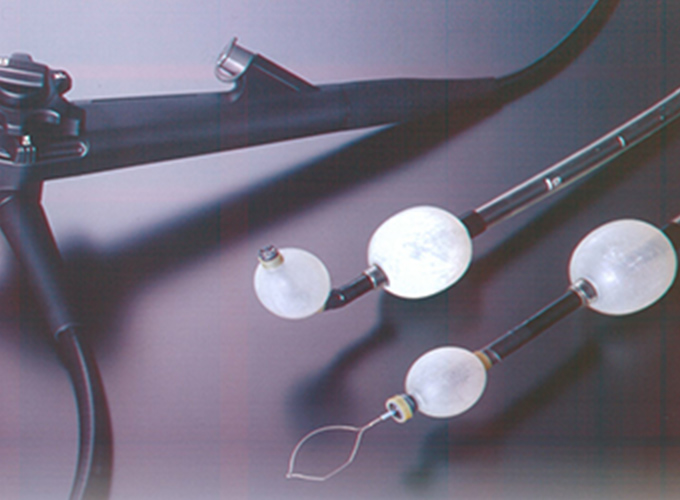

ダブルバルーン内視鏡

ダブルバルーン内視鏡は、小腸の出血性病変を疑う場合や小腸の通過障害、クローン病などの病気が疑われる場合などに適応となります。 ダブルバルーン内視鏡とは、長さ2mの長いスコープとバルーンの付いたオーバーチューブを組み合わせたものです。 小腸内で2つのバルーンを交互に膨らませて固定し、腸管をたたみ込んで内視鏡を進めることで、内視鏡検査が難しかった小腸全体の内視鏡精密検査・治療を可能にしました。

バルーン内視鏡は、X線透視で適宜位置を確認しながら進めます。経口的にも経肛門的にも挿入することが可能で、両方向からの挿入を組み合わせることにより小腸すべてを観察することもできます。観察するだけでなく、出血病変に対して止血したり、ポリープを切除したり、狭いところを広げたりすることもできます。

また、大腸が長かったり癒着のために大腸内視鏡を挿入することが困難な場合にも有用です。